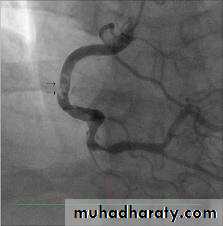

D-Cardiac catheterization :(normal coronary arteries ) to exclude coronary artery disease

$Cardiac catheterization

*Surgery :Outflow tract obstruction can be improved by partial surgical resection (myectomy) to improve symptoms in symptomatic patient who not responsive to medical therapy*By Catheterization : iatrogenic infarction of the basal septum (alcoholic septal ablation) using a catheter-delivered alcohol solution.